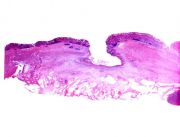

| 2021年12月10日 (五) 13:24 | 27号切片-胃溃疡-大体观.jpg (文件) |  |

69 KB | Cirno.9 | 基于MsUpload的文件上传 | 1 |